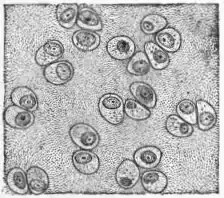

Hyaline Cartilage (fig. 5).—This consists of a number of rounded cells enclosed within a homogeneous matrix. The cells possess an oval nucleus and a granular, often vacuolated cell-body.

Fig. 5.—Hyaline Cartilage. Homogeneous matrix interspersed with groups of cells whose arrangement shows their development by division of the mother cell.

The number of cells present varies considerably in different specimens. In freshly formed cartilage the cells are numerous, the amount of matrix separating them being small. Cartilage grows by a deposition of new matrix by the cartilage cells which thus become more and more separated from one another. After a time the cells divide and subsequently become parted from one another by deposition of fresh matrix between them. The cells are often to be seen in groups of two, three or four cells, indicating the common origin of each group from a parent cell. Towards the surface of the cartilage the cells are often modified in shape tending to become flattened in a direction parallel to the surface. Some of the cells near the surface of a piece of cartilage may be branched, appearing as a transition form between connective tissue corpuscles and typical cartilage cells. This is particularly the case at points where tendon or ligaments are attached. There may often be a deposit of lime salts in the matrix of hyaline cartilage especially in old animals or in the deeper layers of articular cartilage where it is attached to bone. A similar deposit of lime salts is well marked in the superficial parts of the skeleton of the cartilaginous fishes. In the development of animals possessing a bony skeleton, the skeleton is first laid down as hyaline cartilage which subsequently becomes gradually removed, bone being deposited in its place. In the adult, hyaline cartilage is found at the ends of the long bones (articular cartilage), uniting the bony ribs to the sternum (costal cartilage), and forming the cartilages of the nose, trachea and bronchi, &c. This as well as the other forms of cartilage are non-vascular so that the cells must gain their food-stuffs and get rid of their waste products by a process of diffusion through the matrix, a process which must of necessity be slow.